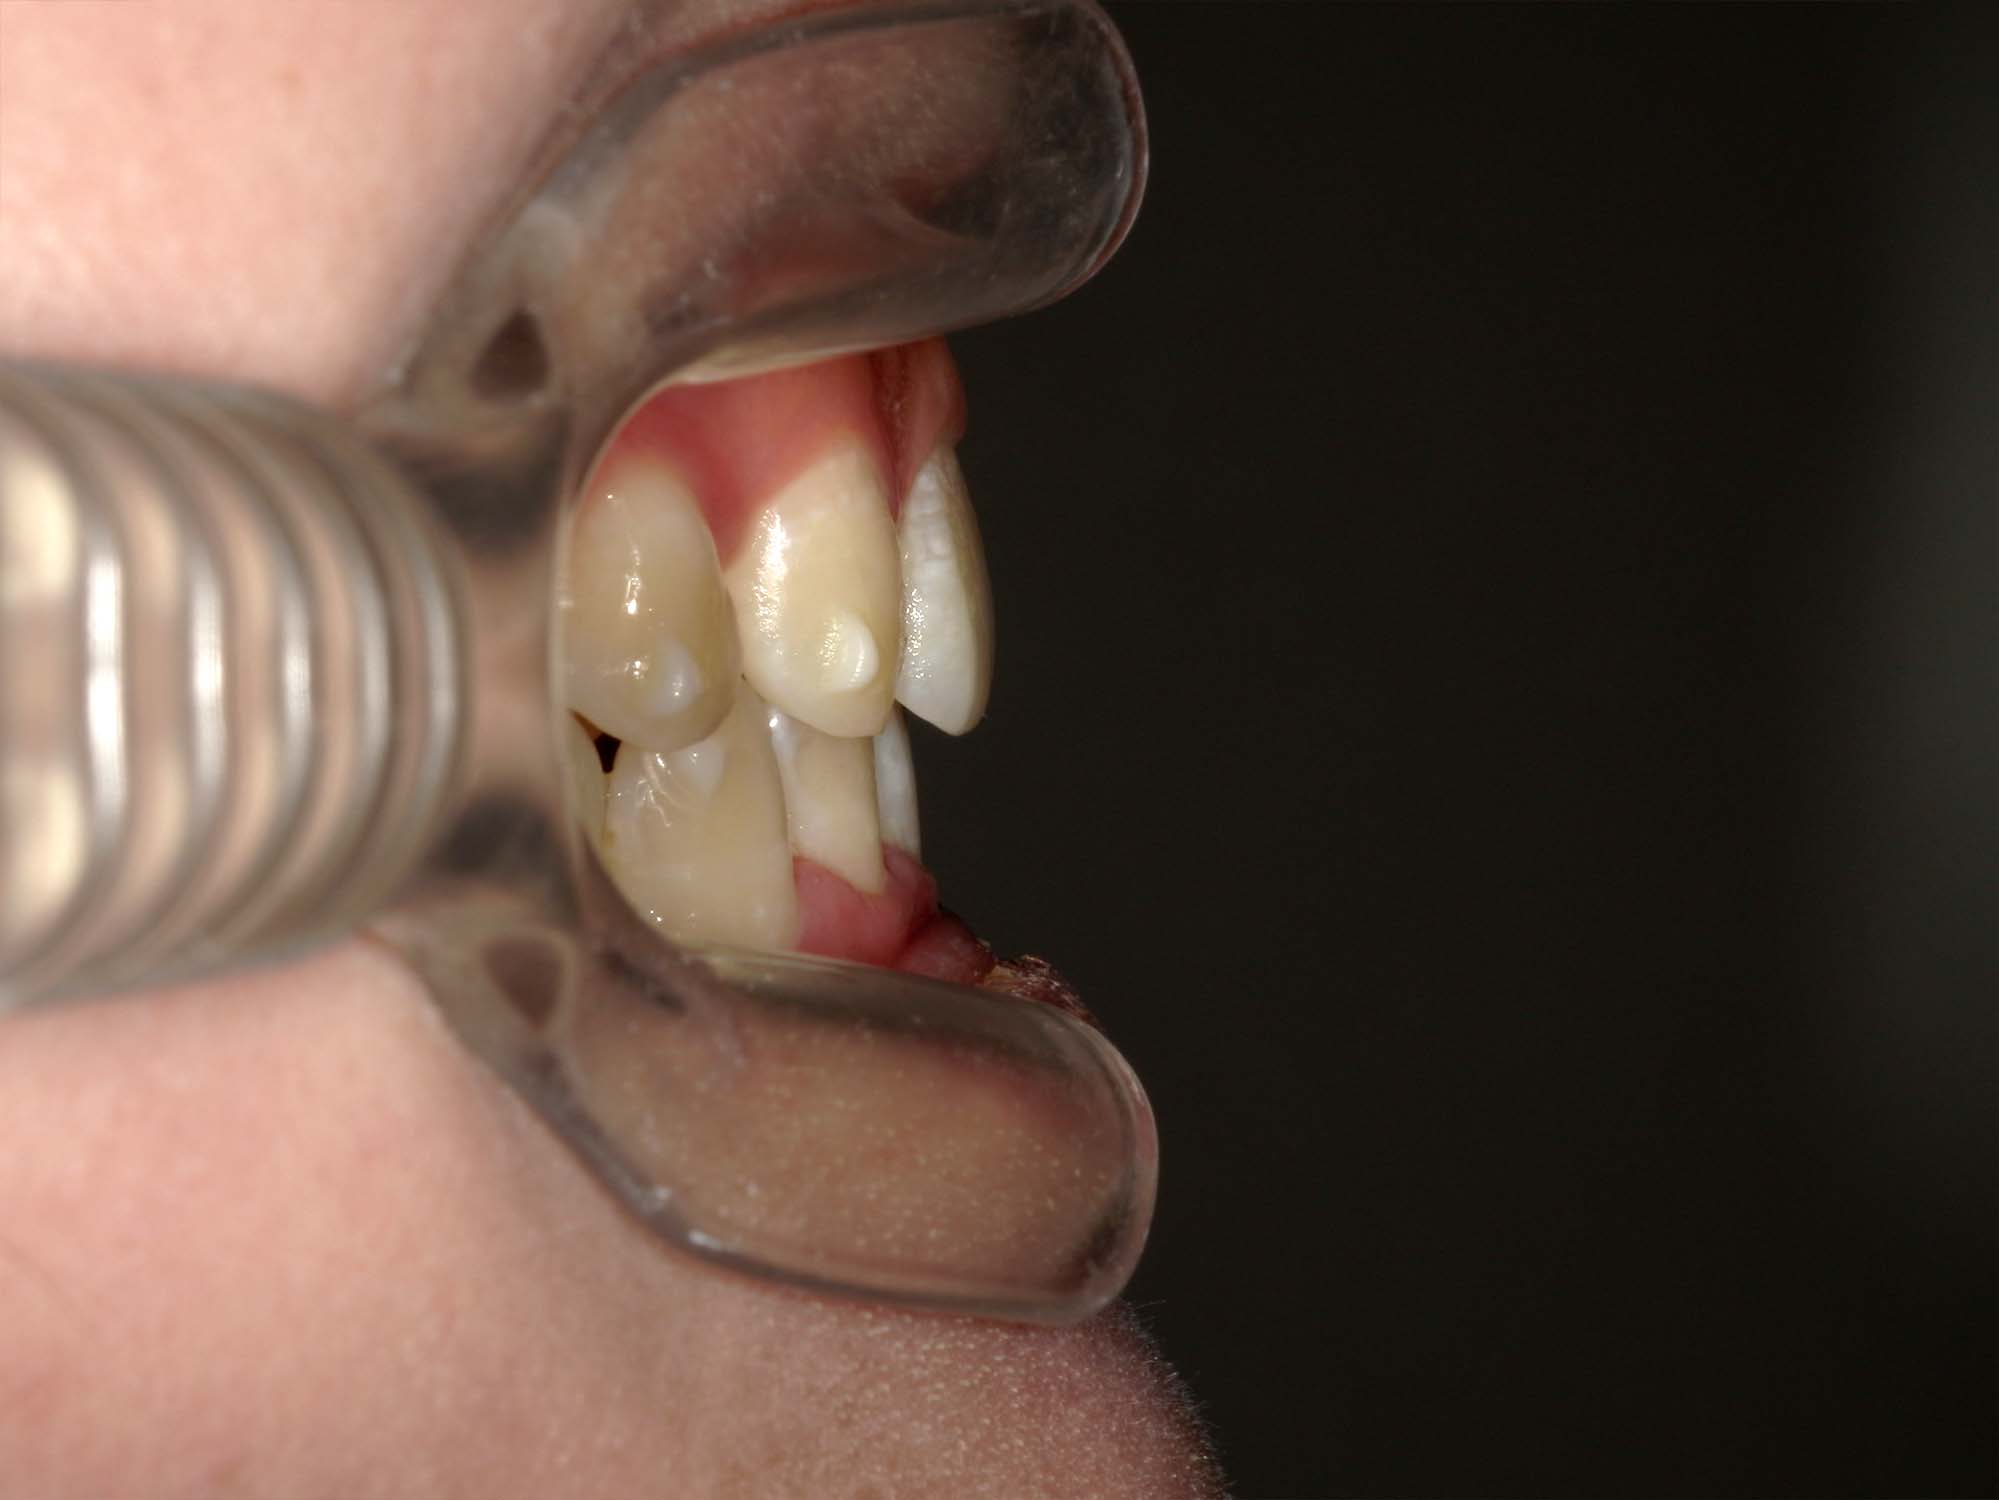

| 年齢・性別 | 21歳 |

|---|---|

| 主訴 | 叢生が気になる・前歯に埋伏歯がある |

| 治療期間・回数 | 6ヶ月 |

| 費用 | 935,000円 |

| 上顎の左側3番が埋伏していたため、上顎左右の3番および親知らずを抜歯し、矯正治療を行いました。 治療開始からおよそ6ヶ月で歯列が整い、審美的にも機能的にも良好な結果が得られた症例です。 |